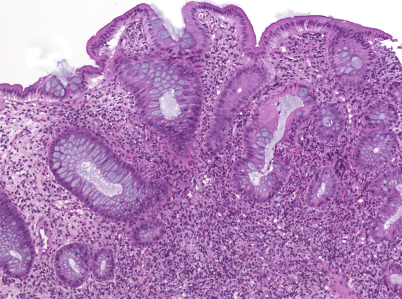

Die histopathologische Diagnose einer chronisch-entzündlichen Darmerkrankung stützt sich auf die Evaluierung von Schleimhautarchitektur und Zellgehalt im Schleimhautstroma [46]. Sowohl eine gestörte Kryptenarchitektur als auch metaplastische Veränderungen, wie z.B. die Panethzellmetaplasie im linken Kolon (bei Colitis ulcerosa) oder die Pylorusdrüsenmetaplasie im terminalen Ileum (bei Morbus Crohn), weisen auf chronische Prozesse hin. Der Zellgehalt im Stroma ist erhöht, kontinuierlich bzw. diffus bei (unbehandelter) Colitis ulcerosa (Abb. 1), diskontinuierlich bei Morbus Crohn (Abb. 2). Neutrophile Granulozyten, im Stroma wie im Epithel (Kryptitis, Kryptenabszesse), sind ein Anzeichen für eine entzündliche Aktivität, ebenso Erosionen und Ulzera.

Abb. 2

Morbus Crohn mit fokaler Entzündung und fissuraler Erosion (ohne Kryptenarchitekturstörung)